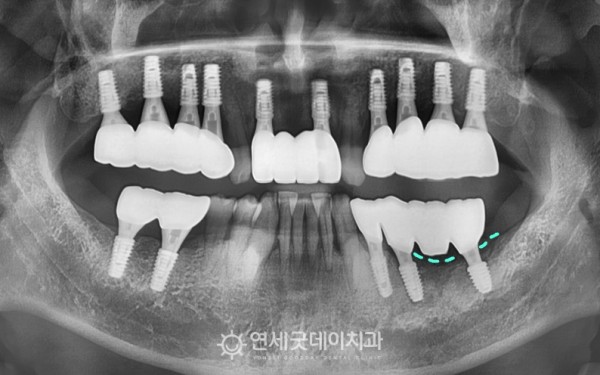

2년 전, 타원에서 전체적으로

임플란트 치료를 받으셨지만

#36,37 부위의 치조골 소실이 상당수 진행된 상태셨습니다.

​엑스레이 상에서 #35 부위에

치근단 병소가 확인되었고,

이로 인해 #36,37 임플란트에

영향을 준 것으로 추정됐습니다.

치료전과 후를 보시면 완전히 내려 앉았던 잇몸뼈가

최대한 두툼하게 재생되며 잘 회복된 모습입니다.